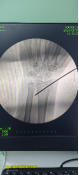

術中透視

患者男性,54歲,外傷致右側脛腓骨開放性骨折8小時,局部可見右側脛骨骨折近端露出···